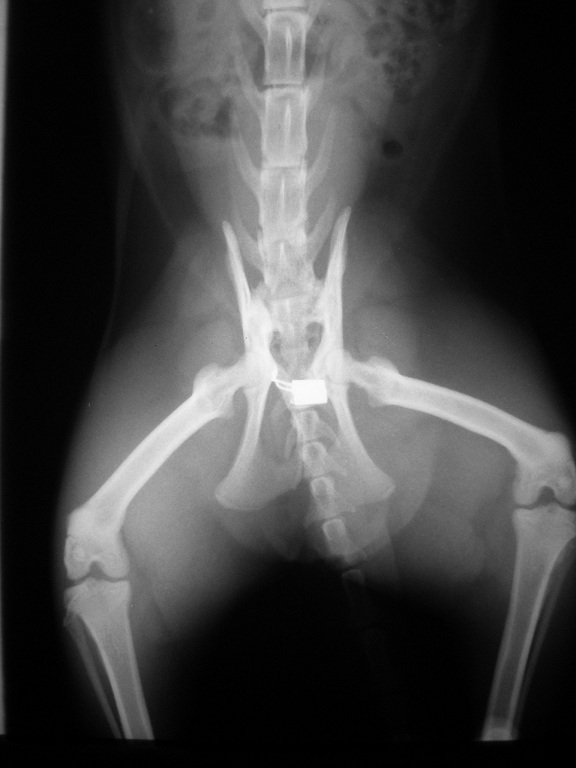

5/28進行半邊骨盆移除手術,

當天手術時間約4-5小時結束,

並且轉往其他醫院住院觀察。

6/2術後回診

艾咪目前已出院回到協會,

但自從手術結束後到這天為止都還沒大過便,

在拍X光照後發現肚子裡約有一天份量的軟便。

醫生說因為艾咪剛動完骨盆移除手術,

後半身虛弱無力還不太能使上力大便,

因此杜化液(軟便劑)還是要繼續輔助使用,

之後再依照大便軟硬程度做調整,

如兩天後還是沒大便則需要通知醫生。